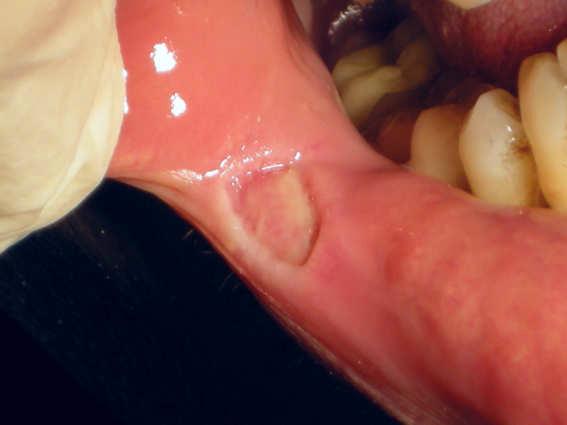

Dr. Valter Pirazzoli

Diode Laser 810nm

Power: 2,0 Watt,

CW

Fibre 400 micron